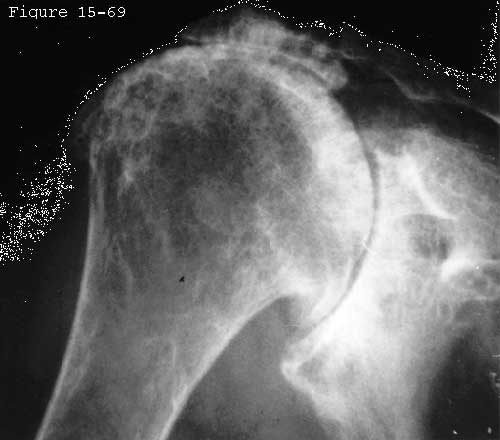

Small avulsed fragments of the tuberosity may be seen in younger patients with cuff lesions (see figure 1) (not to be confused with calcific deposits). Chronic cuff disease may be accompanied by sclerosis of the undersurface of the acromion (the "sourcil" or eyebrow sign) (see figure 2) traction spurs in the coracoacromial ligament from forced contact with the cuff and the humeral head and changes at the cuff insertion to the humerus (see figures 3-5). (Diamond 1964 Inman Saunders 1944 Johansson and Barrington 1984 Meyer 1931 Weiner and Macnab 1970b) Radiographs may also reveal evidence of some of the conditions possibly associated with cuff disease such as acromioclavicular arthritis chronic calcific tendinitis tuberosity displacement and the like (see figures 6-8). With larger tears radiographs reveal upward displacement of the head of the humerus with respect to the glenoid and acromion (see figures 9-12). (Colachis and Strohm 1971 Diamond 1964 Ismail Balakishnan 1969 Julliard 1933 Lilleby 1984 Weiner and Macnab 1970b) Kaneko et al (Kaneko DeMouy 1995) found that superior migration of the humerus and deformity of the greater tuberosity were the most sensitive and specific manifestations of massive cuff deficiency. In cuff tear arthropathy the humeral head may have lost the prominence of the tuberosities (become "femoralized") and the coracoid acromion and glenoid may have formed a deep spherical socket (become "acetabularized") (see figures 5 and 13-15).

Click to enlarge

Figure 14